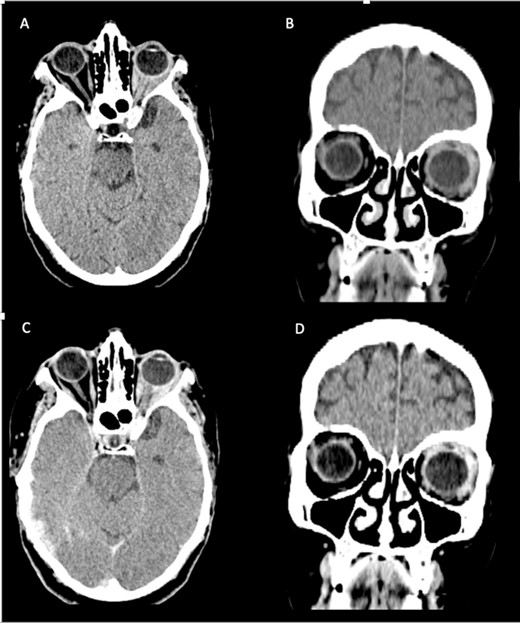

The CT scan displayed a tissue infiltration and bulking of the left superior and lateral extraocular rectus muscle (Fig. 1).

Axial and coronal cerebral CT scans show enlargement of the left lateral and superior rectal muscles (A–B), with slight enhancement (C–D).